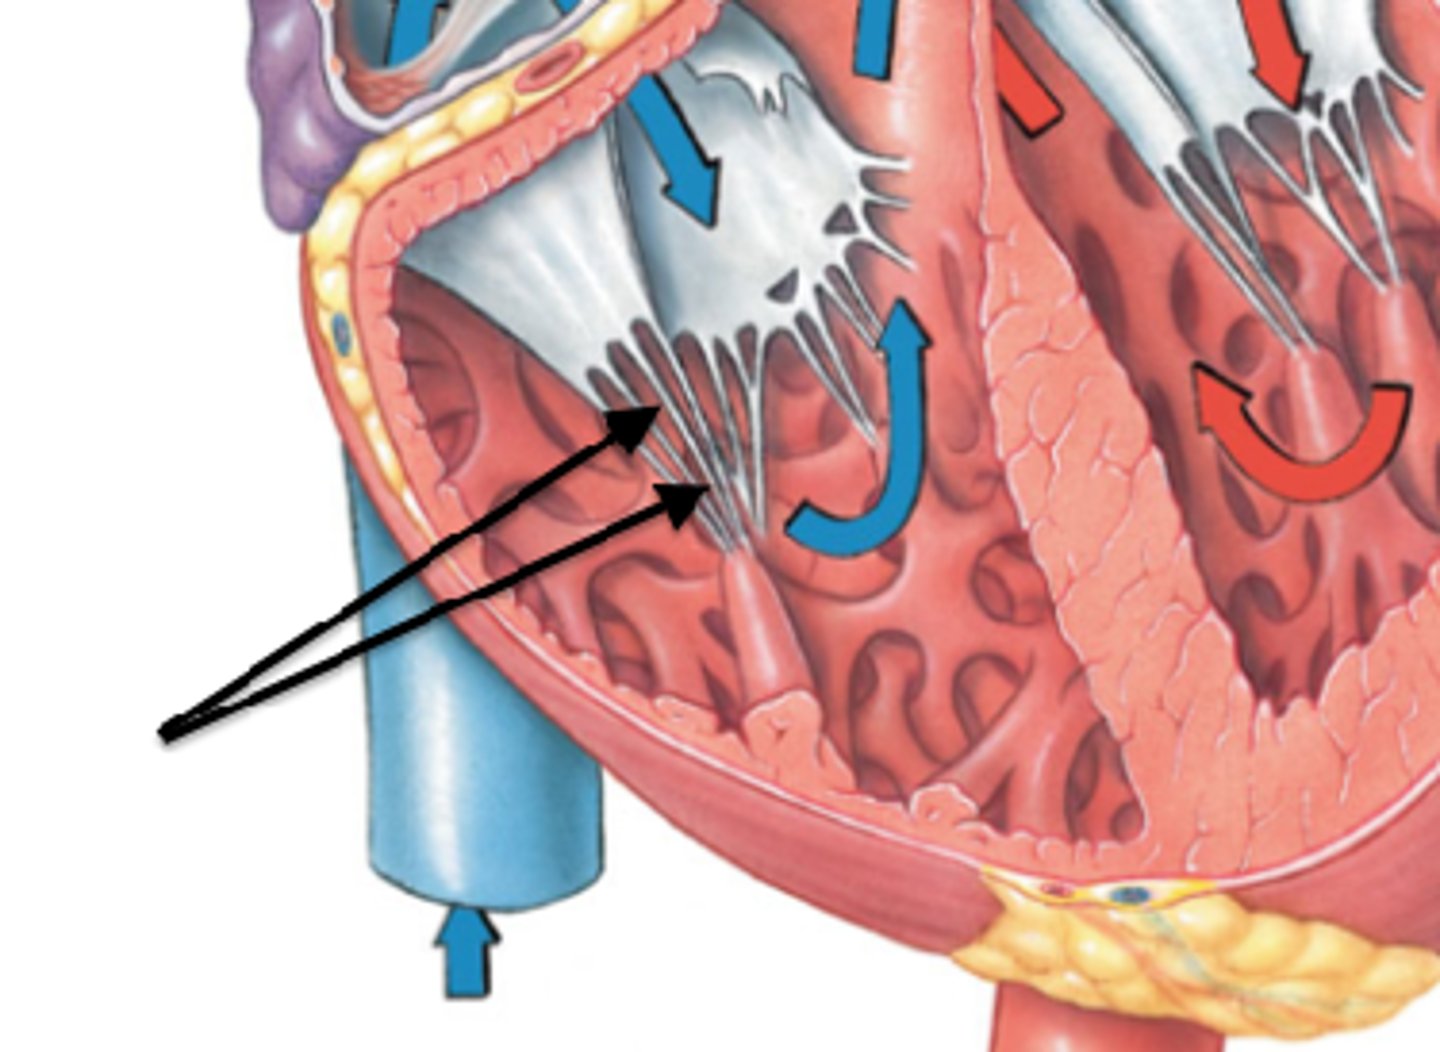

tricuspid valve

Structure; closed door, three flaps

26

R papillary muscles

Structure; right ventricle,

orange part of the carrot

tendinous cords

Feature; right ventricle

leaves of carrot

trabeculae carneae

Structure; in right ventricle

dirt of carrot